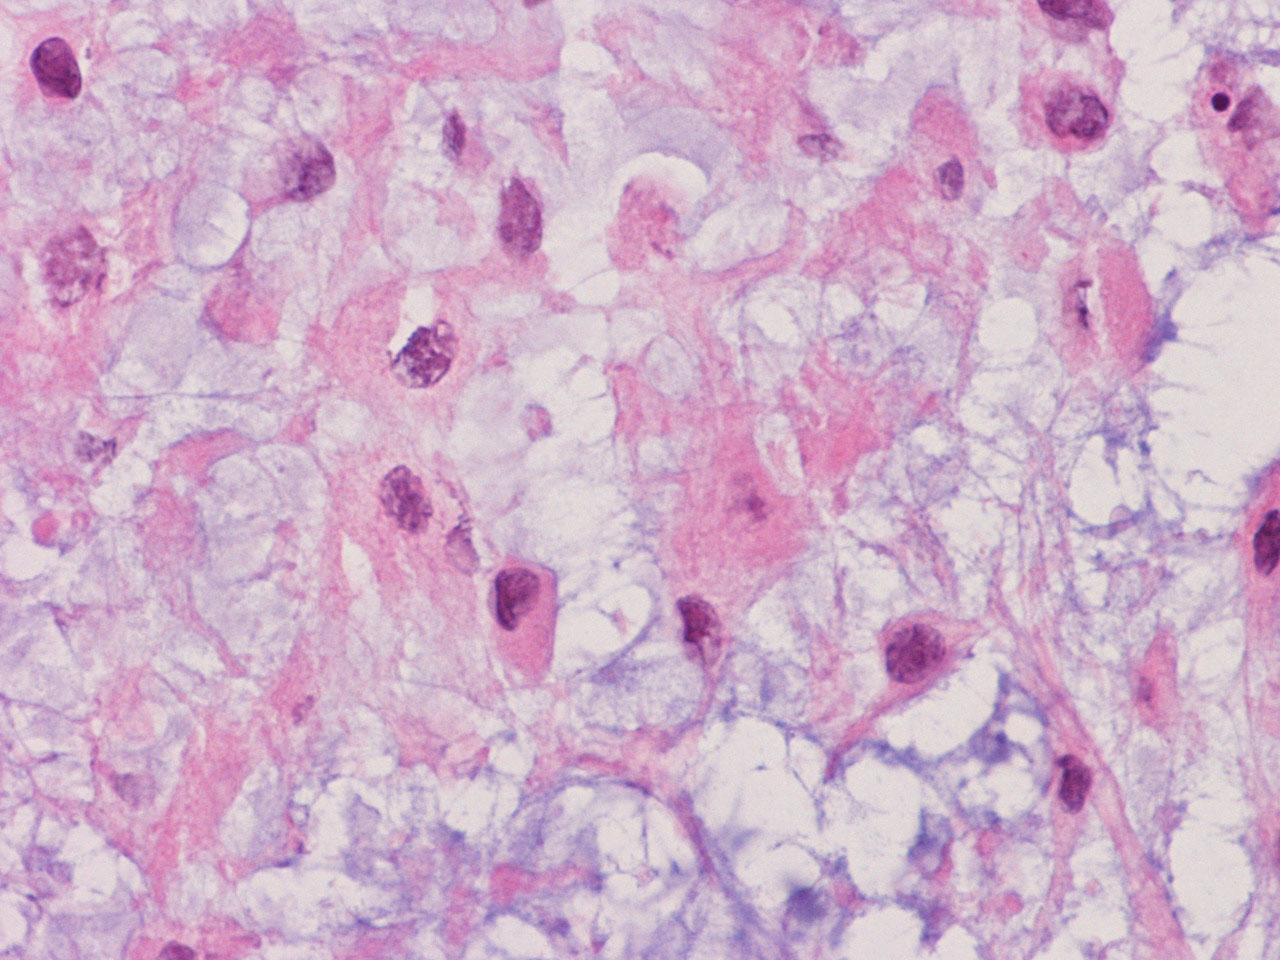

At the time of operation, a cytologic squash preparation (H&E) was prepared (Panels BC, and D). On low magnification, the lesion is composed of large clusters of eosinophilic cells with centrally located nuclei. There is some bluish acellular substance admixed with the tumor cells (Panel B). If you pay attention, some of the cells are arranged in short chains (arrows in Panel C). This is a frequently seen phenomenon in chordoma. On high magnification, the cells have centrally located medium sized to large, hyperchromatic nuclei. The cytoplasm is finely eosinophilic but not particularly bubbly  (Panel D). The frozen sections (Panels E and Freflect the cytologic features. The tumor is composed of solid sheets of large tumor cells admixed with small amount of fibrous areas, mild chronic inflammatory cell infiltration and hemosiderin depositions (Panel E). On high magnification, the tumor cells are admixed with bluish extracellular material.  The cytoplasm is coarsely granular with fine bubbles. The permanent sections (Panel G and Hshow similar features. And the bubbly cytoplasm is more prominent in the permanent sections (Panel H). Focal bone invasion is present (Panel I). The cytoplasmic vacuoles are best appreciated in the semithin section (Panel M). Results of special studies are as follows:

The characteristic histologic findings in chordomas are large polygonal cells with distinct cell membrane and the vacuolated physaliphorous cytoplasm, the term deriving from the Greek physalis, or "bubble. The vacuolated or physaliphorous cells are best appreciated in cytologic smears or squash preparations. Tumor cells grow in small nests and cords within a myxoid/chondroid matrix and demonstrate round, sometimes rather uniform nuclei with low nuclear-to-cytoplasmic ratios. The tumor cells tend to adhere into clusters and cords. The classic large physaliphorous cell has a centrally located nucleus surrounded by a narrow rim of cytoplasm that in turn, is encircled by a ring of more peripherally located cytoplasmic vacuoles. Nuclear grade is not particularly high in some cases but many of them have clearly recognizable nuclear pleomorphism. Occasional large, atypical cells are present. These nuclear changes should not be present in benign notochordal cell tumor and ecchordosis physaliphora/fetal vestige [Amer & Hameed, 2010]